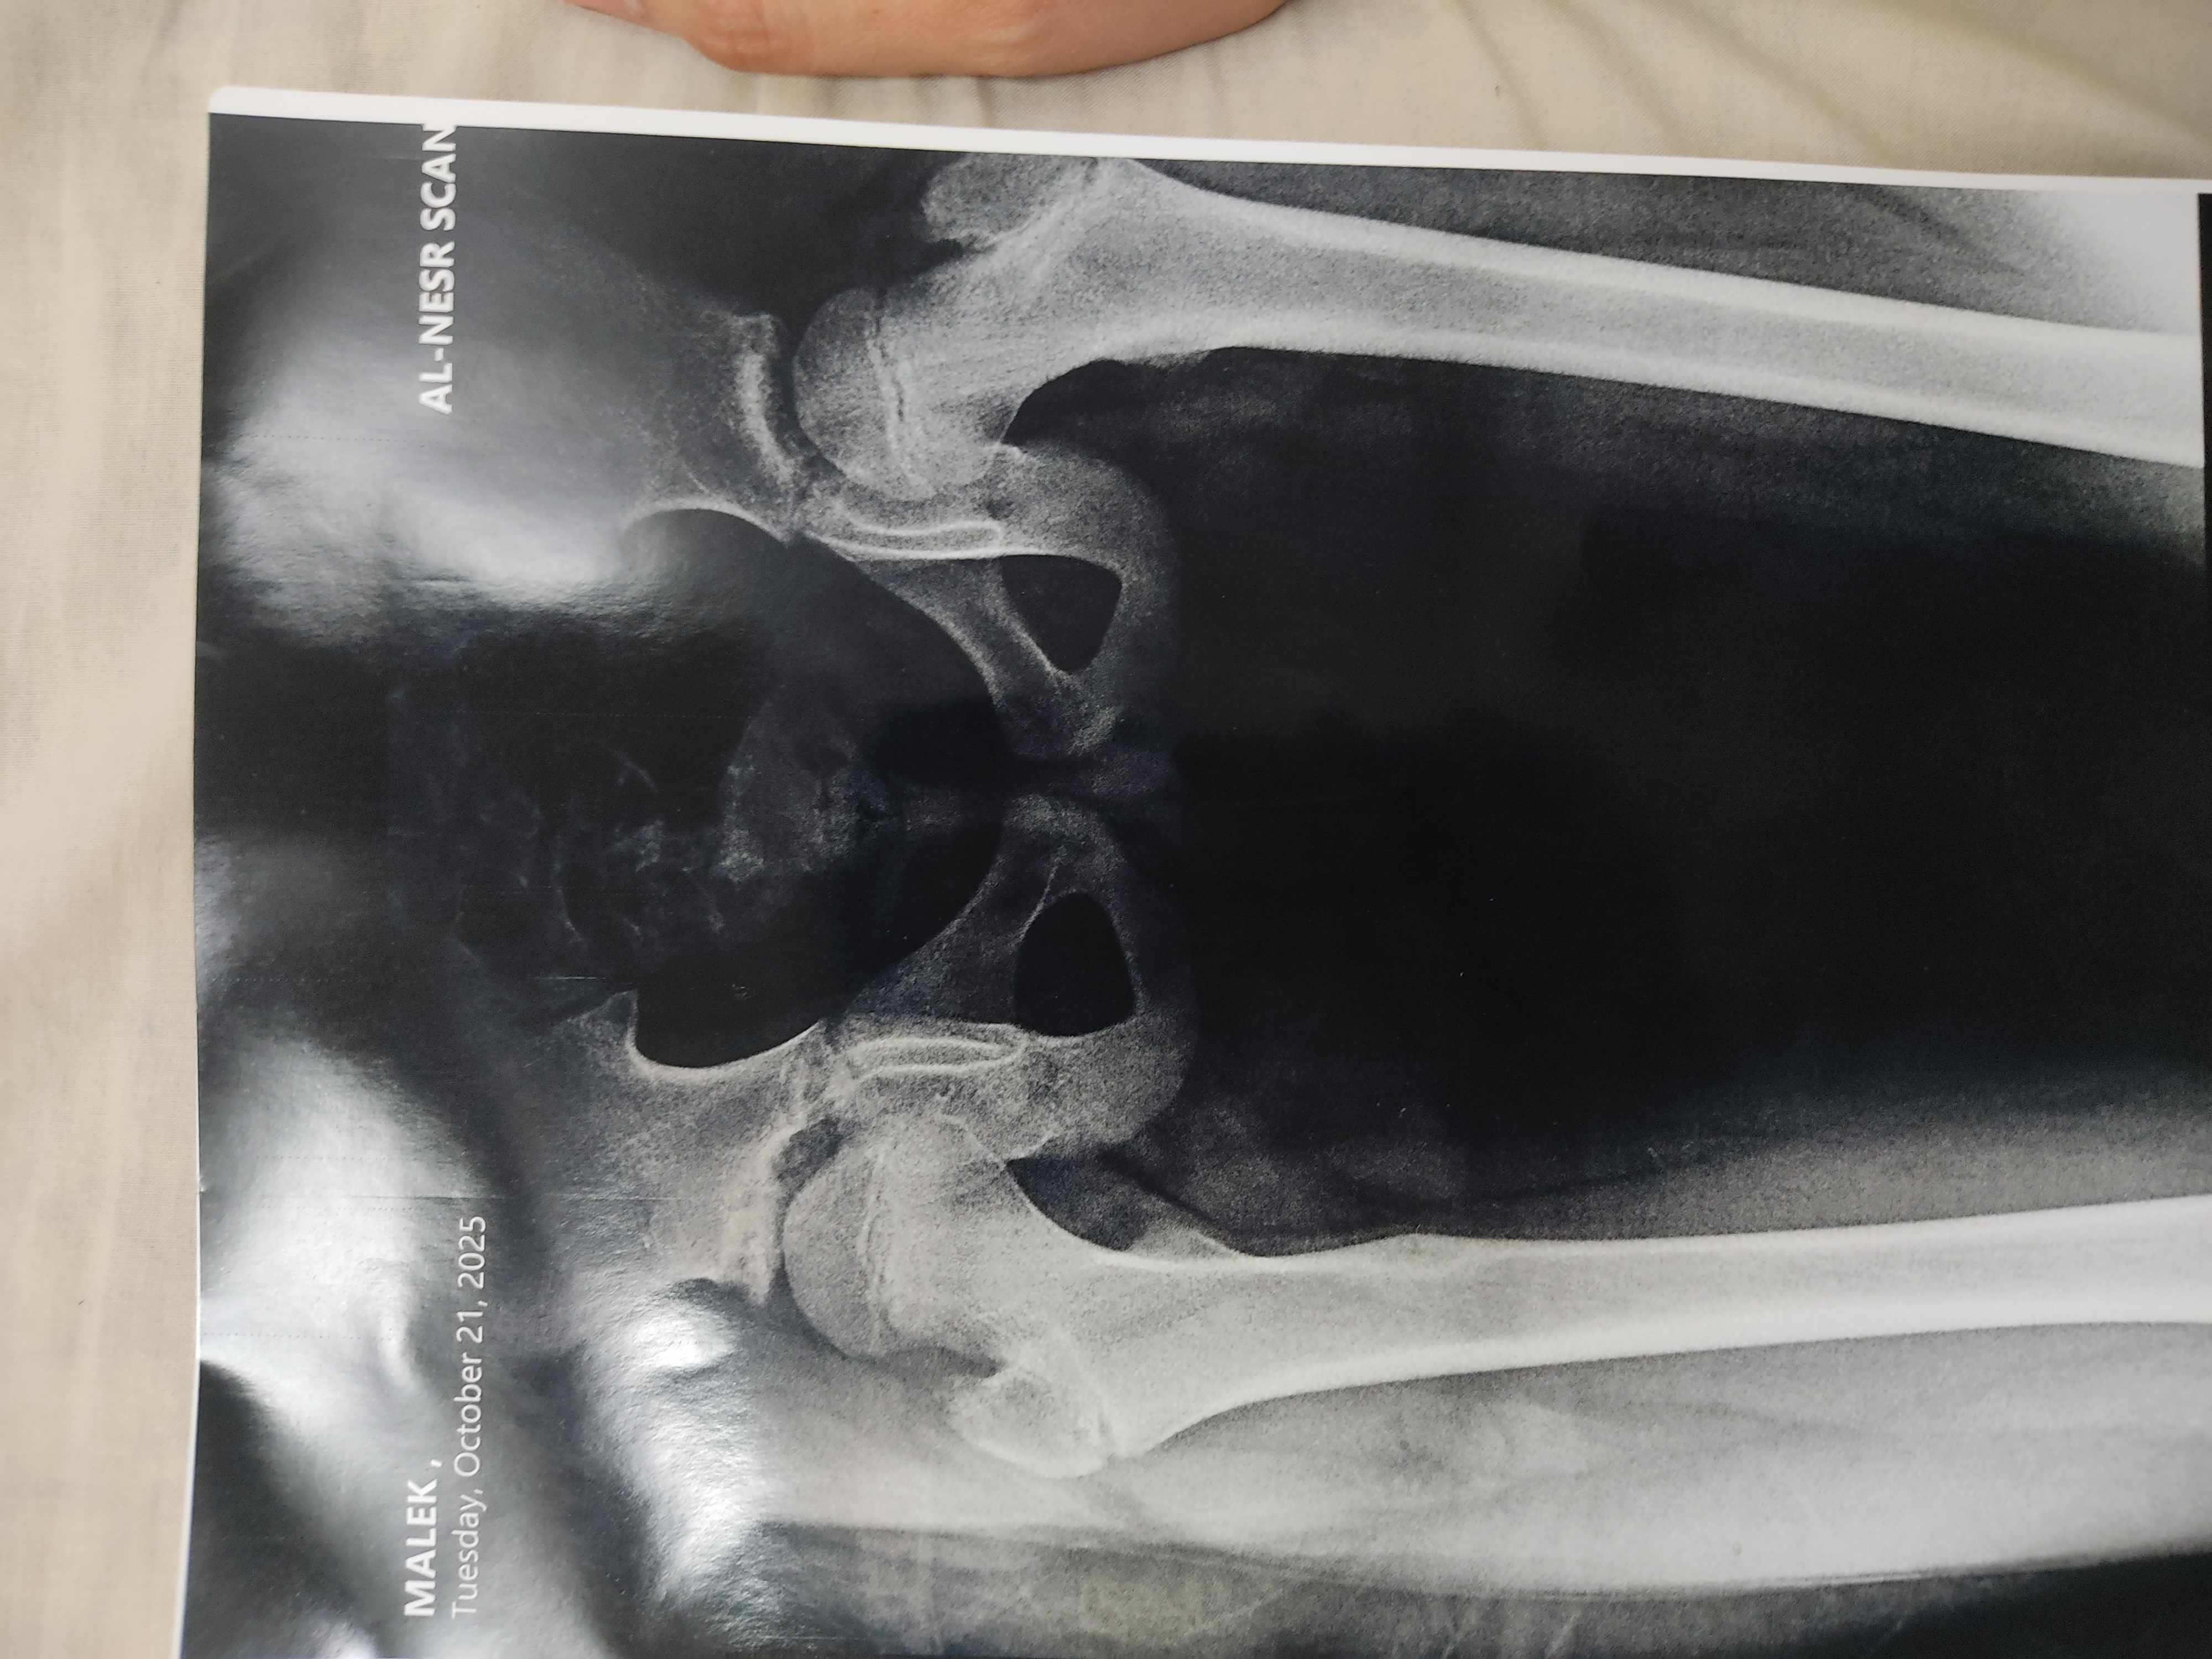

عملت اشاعه لابنى و الدكتور اخبرنى ان عظمه الفخذ بها تزحزح بسيط عن مكانها بمعنى ان كان سبحدث خلع و طلب من ابنى ركوب العجله بكثره ثم اعاده الاشاعه مرة اخرى بعد ست شهور فهل يمكن ان ترجع العظمه مكانها باذن الله بدون تدخل حراجى

صورة مرفقة

شاهدت الصورة

وهي طبيعية

والمطلوب مراقبة الطفل

وفي حال كان هناك عرج أو الم مستمر ينصح بإجراء تصوير رنين مغناطيسي للمفصل MRI

ولا ارى ما يدعو للقلق حالياً

ولا حاجة للجراحة

فقط مراقبة